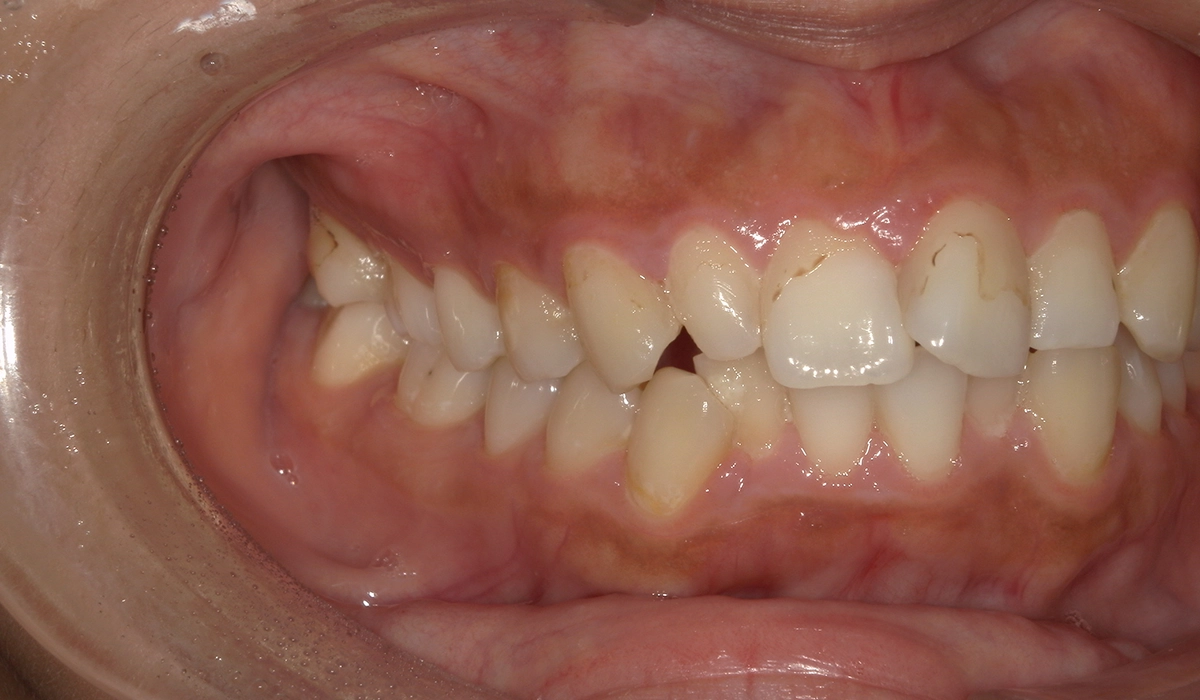

今回ご紹介する患者様は、上下の歯並びのガタツキを気にされており、矯正検査後叢生Ⅱ級と診断いたしました。

術前:右側

術後:右側